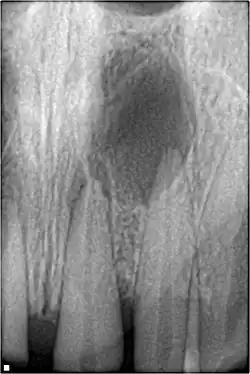

An odontogenic infection is an infection that originates within a tooth or in the closely surrounding tissues.[1] The term is derived from odonto- (Ancient Greek: ὀδούς, odoús – 'tooth') and -genic (Ancient Greek: -γενής, -γενῶς; -genḗs, -genôs – 'birth'). The most common causes for odontogenic infection to be established are dental caries, deep fillings, failed root canal treatments, periodontal disease, and pericoronitis.[2] Odontogenic infection starts as localised infection and may remain localised to the region where it started, or spread into adjacent or distant areas.

It is estimated that 90–95% of all orofacial infections originate from the teeth or their supporting structures and are the most common infections in the oral and maxilofacial region.[3] Odontogenic infections can be severe if not treated and are associated with mortality rate of 10 to 40%.[4] Furthermore, about 70% of odontogenic infections occur as periapical inflammation, i.e. acute periapical periodontitis or a periapical abscess.[3] The next most common form of odontogenic infection is the periodontal abscess.[3] Despite being more common in underprivileged regions, odontogenic infections affect people from all over the world, even in developed countries.[5]

Sinusitis is inflammation of the paranasal air sinuses. Odontogenic sinusitis is an inflammatory condition of the paranasal sinuses that is the result of dental pathology, most often resulting from prior dentoalveolar procedures, infections of maxillary dentition, or maxillary dental trauma.[6] Infections associated with teeth may be responsible for approximately 20% of cases of maxillary sinusitis.[7] The cause of this situation is usually a periapical or periodontal infection of a maxillary posterior tooth, where the inflammatory exudate has eroded through the bone superiorly to drain into the maxillary sinus. Medical management and treatment of the underlying dental pathology remains a critical initial step in the treatment of odontogenic sinusitis, however recent literature suggests that a significant portion of patients may require endoscopic sinus surgery for successful disease resolution.[6] Once an odontogenic infection involves the maxillary sinus, it is possible that it may then spread to the orbit or to the ethmoid sinus.[7]